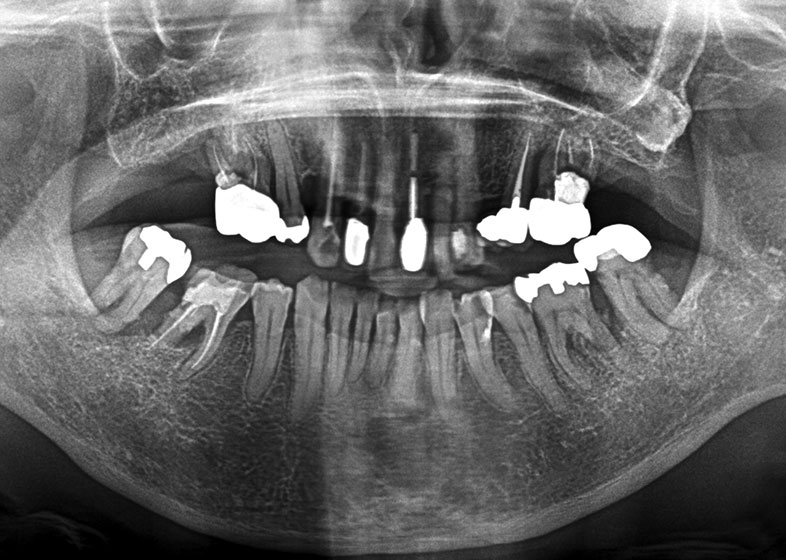

抜歯例

| 年齢 | 24歳 |

|---|---|

| 症状、主訴 | 違和感あり |

| 治療内容 | 左下埋伏歯抜歯 |

| 費用 | トータル約8,000円 |

| 治療回数 | 3回 |

| メリット | 歯周病、虫歯の予防ができる |

| デメリット | 下顎埋伏歯抜歯については神経麻痺の症状が出る可能性がある。 |

| 院長コメント | 左下8/一般的な埋伏歯。比較的簡単です。 |

| 年齢 | 55歳 |

| 症状、主訴 | 症状とくになし |

| 治療内容 | 左上埋伏歯抜歯 |

| 治療回数 | 2回 |

| メリット | 左上7相当部へのインプラントを打つ為に抜歯 |

| デメリット | 上顎洞への迷入の危険性がありましたが、特に問題なく抜く事が出来ました。 |

| 院長コメント | 左下8/難しい症例でしたが、当院で抜歯しています。 |